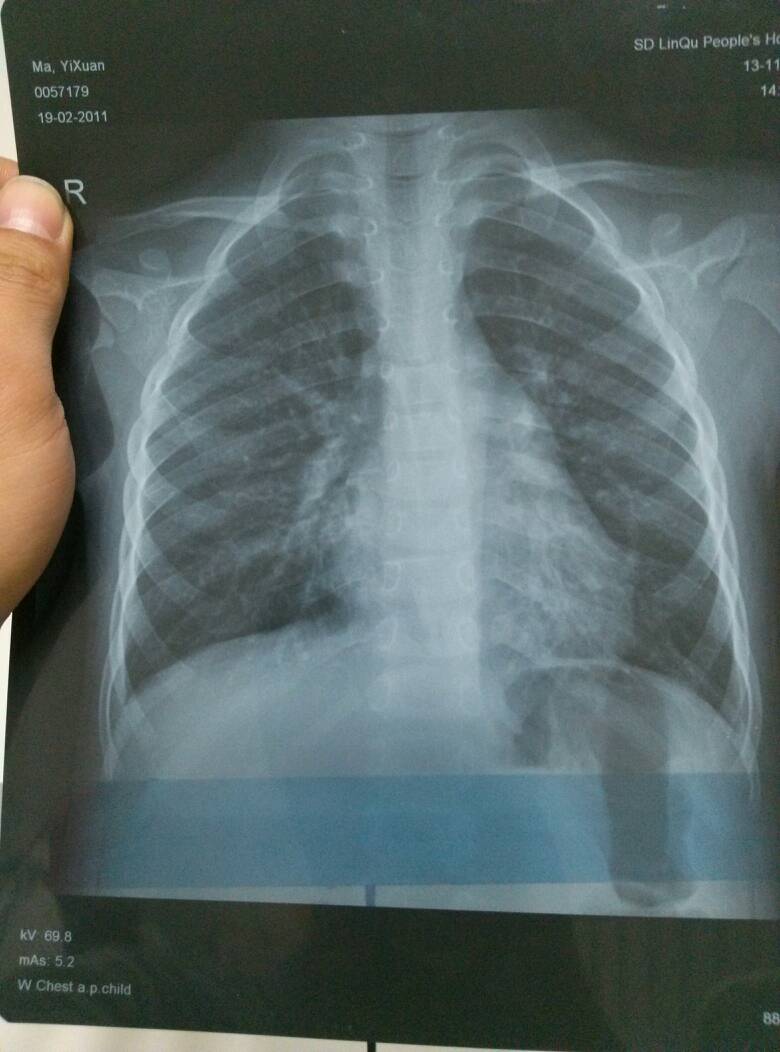

轻度肺炎胸片

小孩四岁发烧不退诊断为肺炎,帮忙看下两次片子是否好了